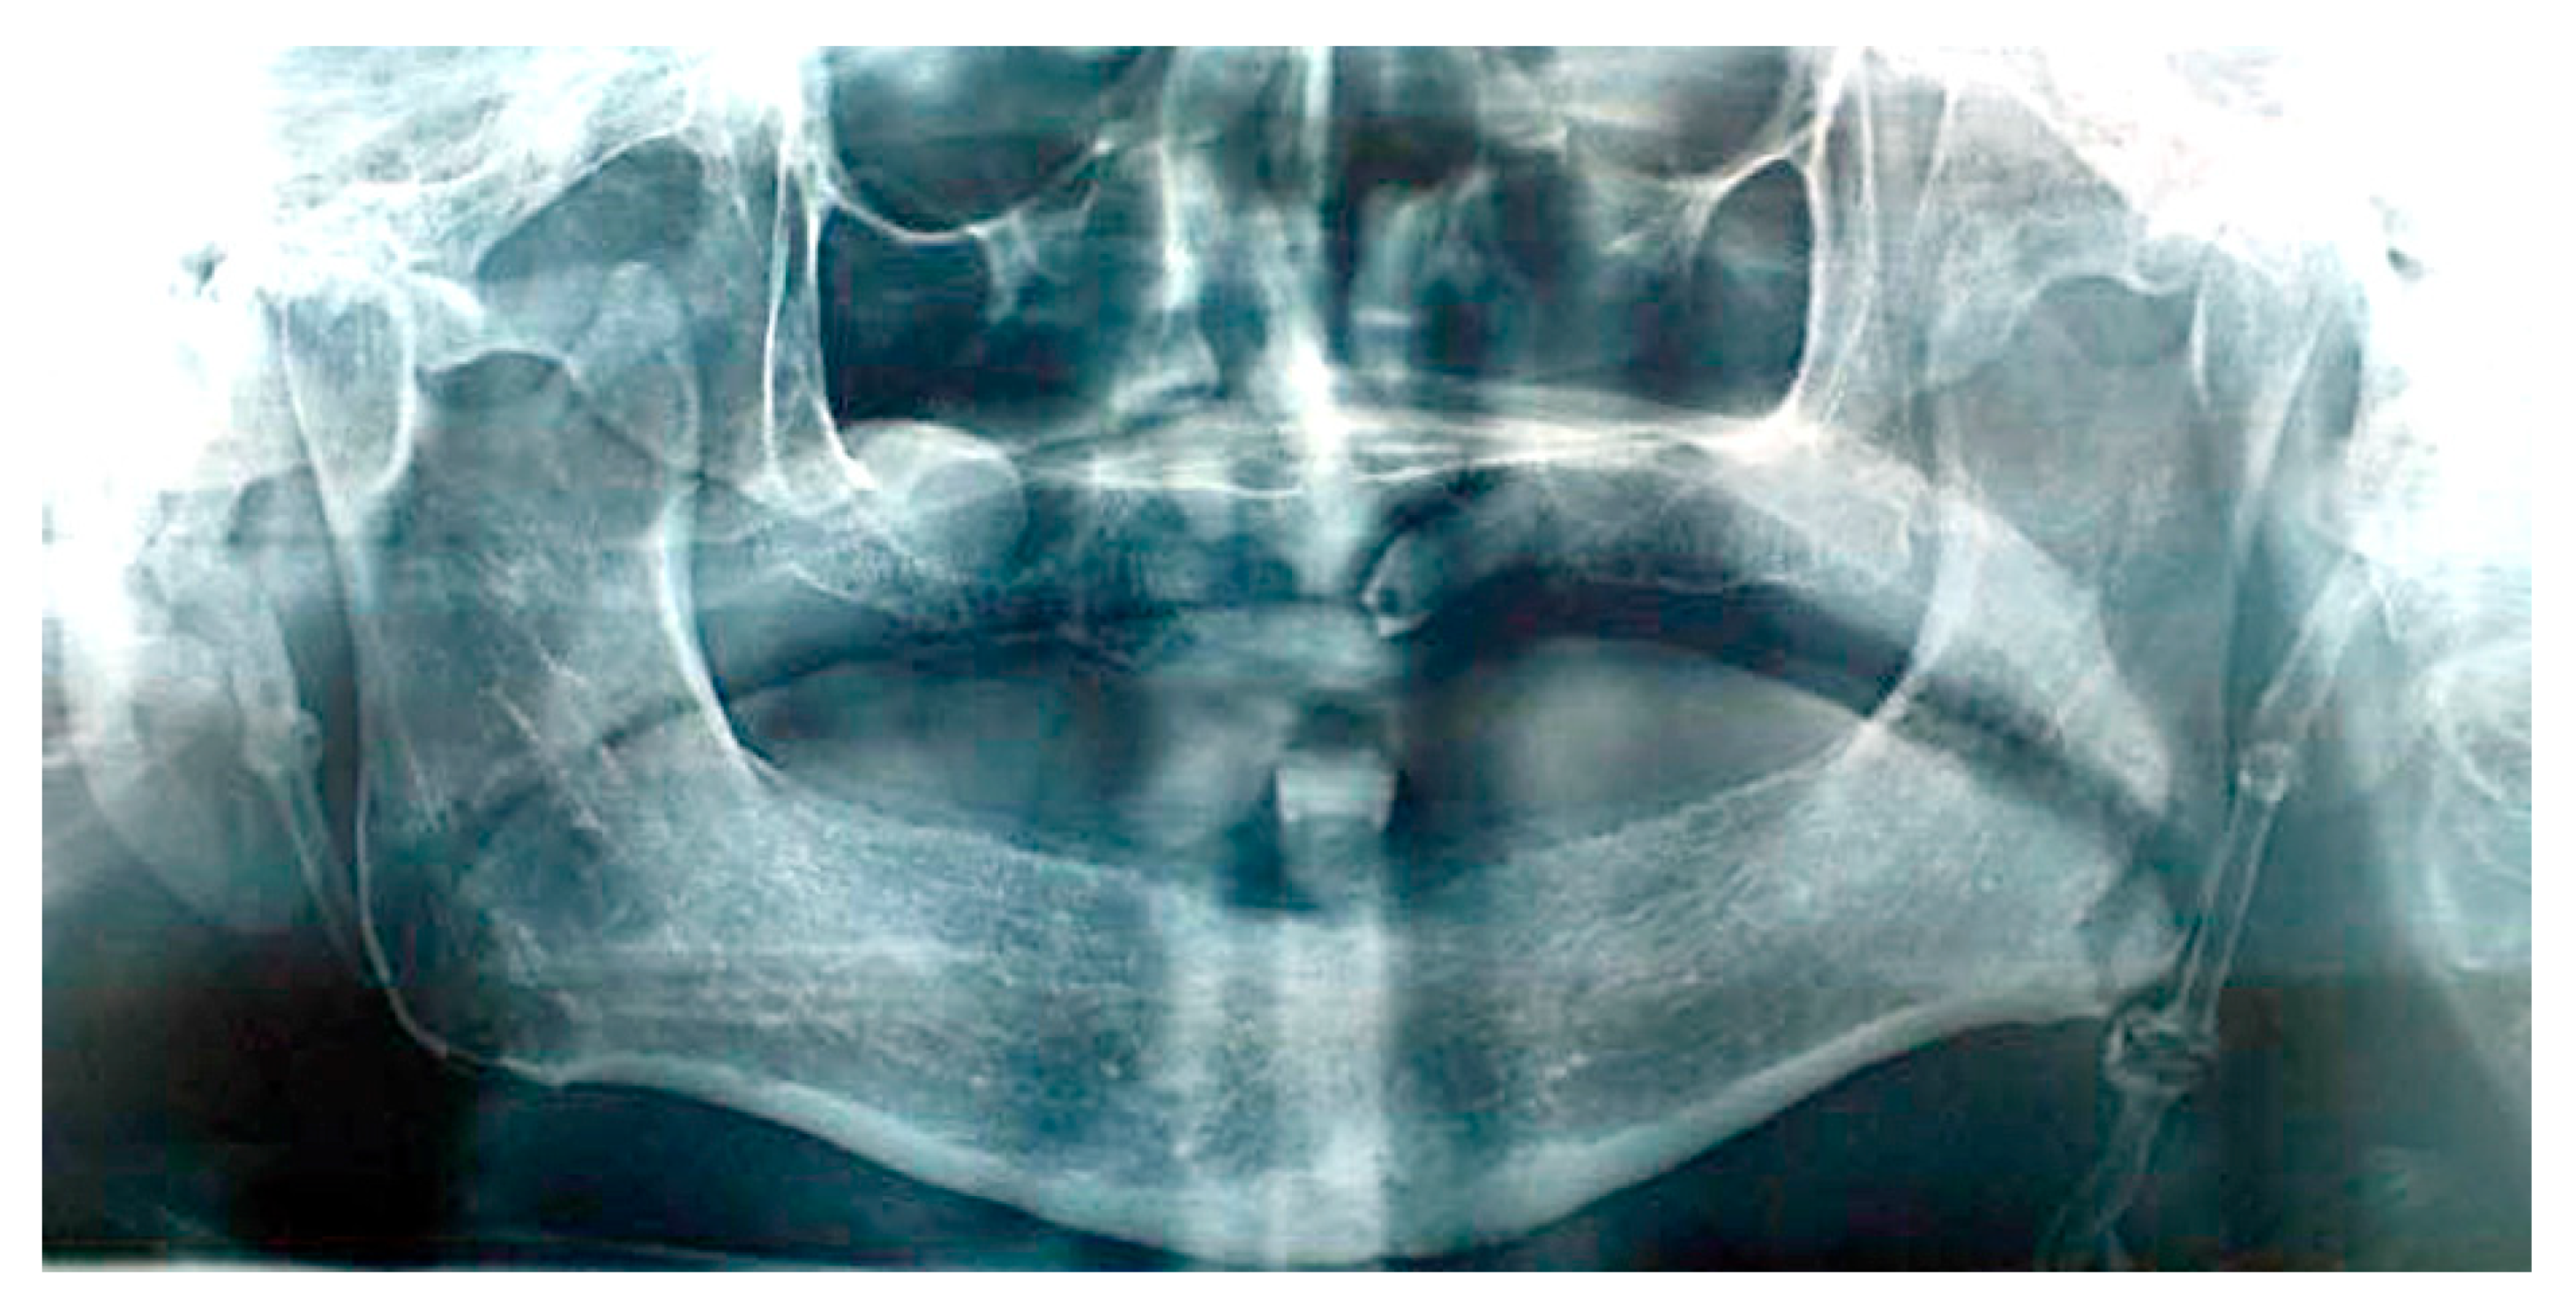

The patient’s orofacial region was thoroughly examined with no clinical findings indicating the cause of her pain episodes. However, oropharyngeal examination showed severe tenderness and pain on palpation in the right tonsillar region, with motion pain occurrence during head horizontal rotation. Panoramic X-ray acquisition showed pathological elongation of the right styloid process, like a “thorn” with a length of 49 mm by manual measurement with a ruler (Figure 1).

Figure 1. Cropped panoramic image showing pathologically elongated styloid process ending at the inner side of angle of mandible. The length of styloid process is 46 mm (conventional manual measurement with straight ruler).

Patient #1 is categorized in the group confirming diagnosis of true Eagle’s syndrome and scheduled for surgery. After preparation for general anesthesia, surgery was performed by the extraoral trans cervical per via approach into the parapharyngeal space, for identification of styloid process, which was subsequently surgically removed for half of its length (~25 mm), seen in repeated panoramic X-ray acquisition (Figure 2).

In the panoramic view, when the styloid process is elongated, it attains over one third of the mandibular ramus length [18], which is presented on the panoramic image in patient #1. Taking all the obtained clinical facts into account (clinical symptoms and panoramic image) in the described case, diagnosis with proper subsequent surgical treatment of true Eagle’s syndrome was made in patient #1.